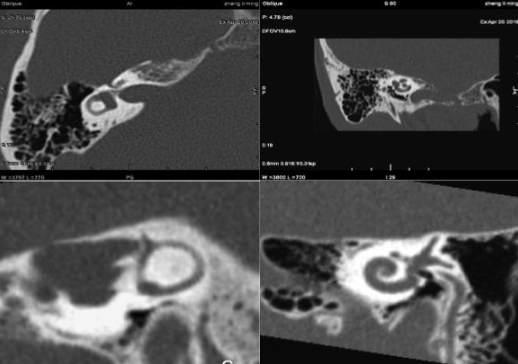

培训团队针对各中心的16/64排CT、1.5T磁共振等设备着重进行了后处理和增强扫描流程教学,同时开展设备培训质控工作,对培训方式、志愿者安排、培训考核、图像质量等进行质控和记录,针对中心医师和技术员的诊断扫描习惯对序列进行优化并进行参数调整和图像质控。

江西铅山影像中心CT培训工作

辽宁沈阳影像中心CT培训工作